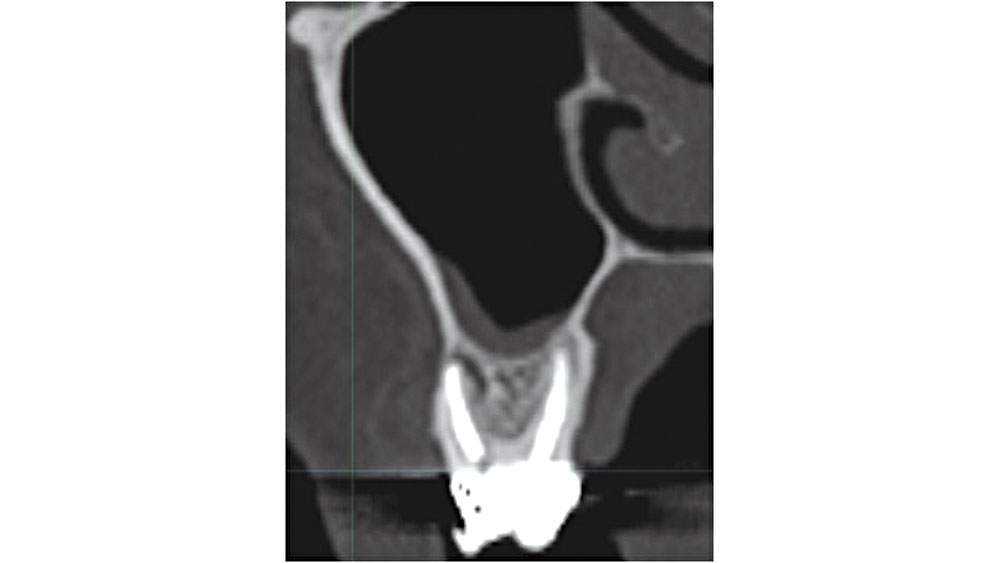

Maxillary Compromised Sites

In the maxillary molar areas, approximately 42 percent of the roots extend into the sinus proper.7 When the tooth is extracted, the sinus membrane may be perforated and an exposure may occur. If grafting is completed, bone graft material may be introduced into the sinus, leading to the possibility of an acute rhinosinusitis. In addition, care should be exercised in curetting soft-tissue lesions, as complications may result (Fig. 9).

Figure 9

Figure 9: Maxillary molar proximity to maxillary sinus.